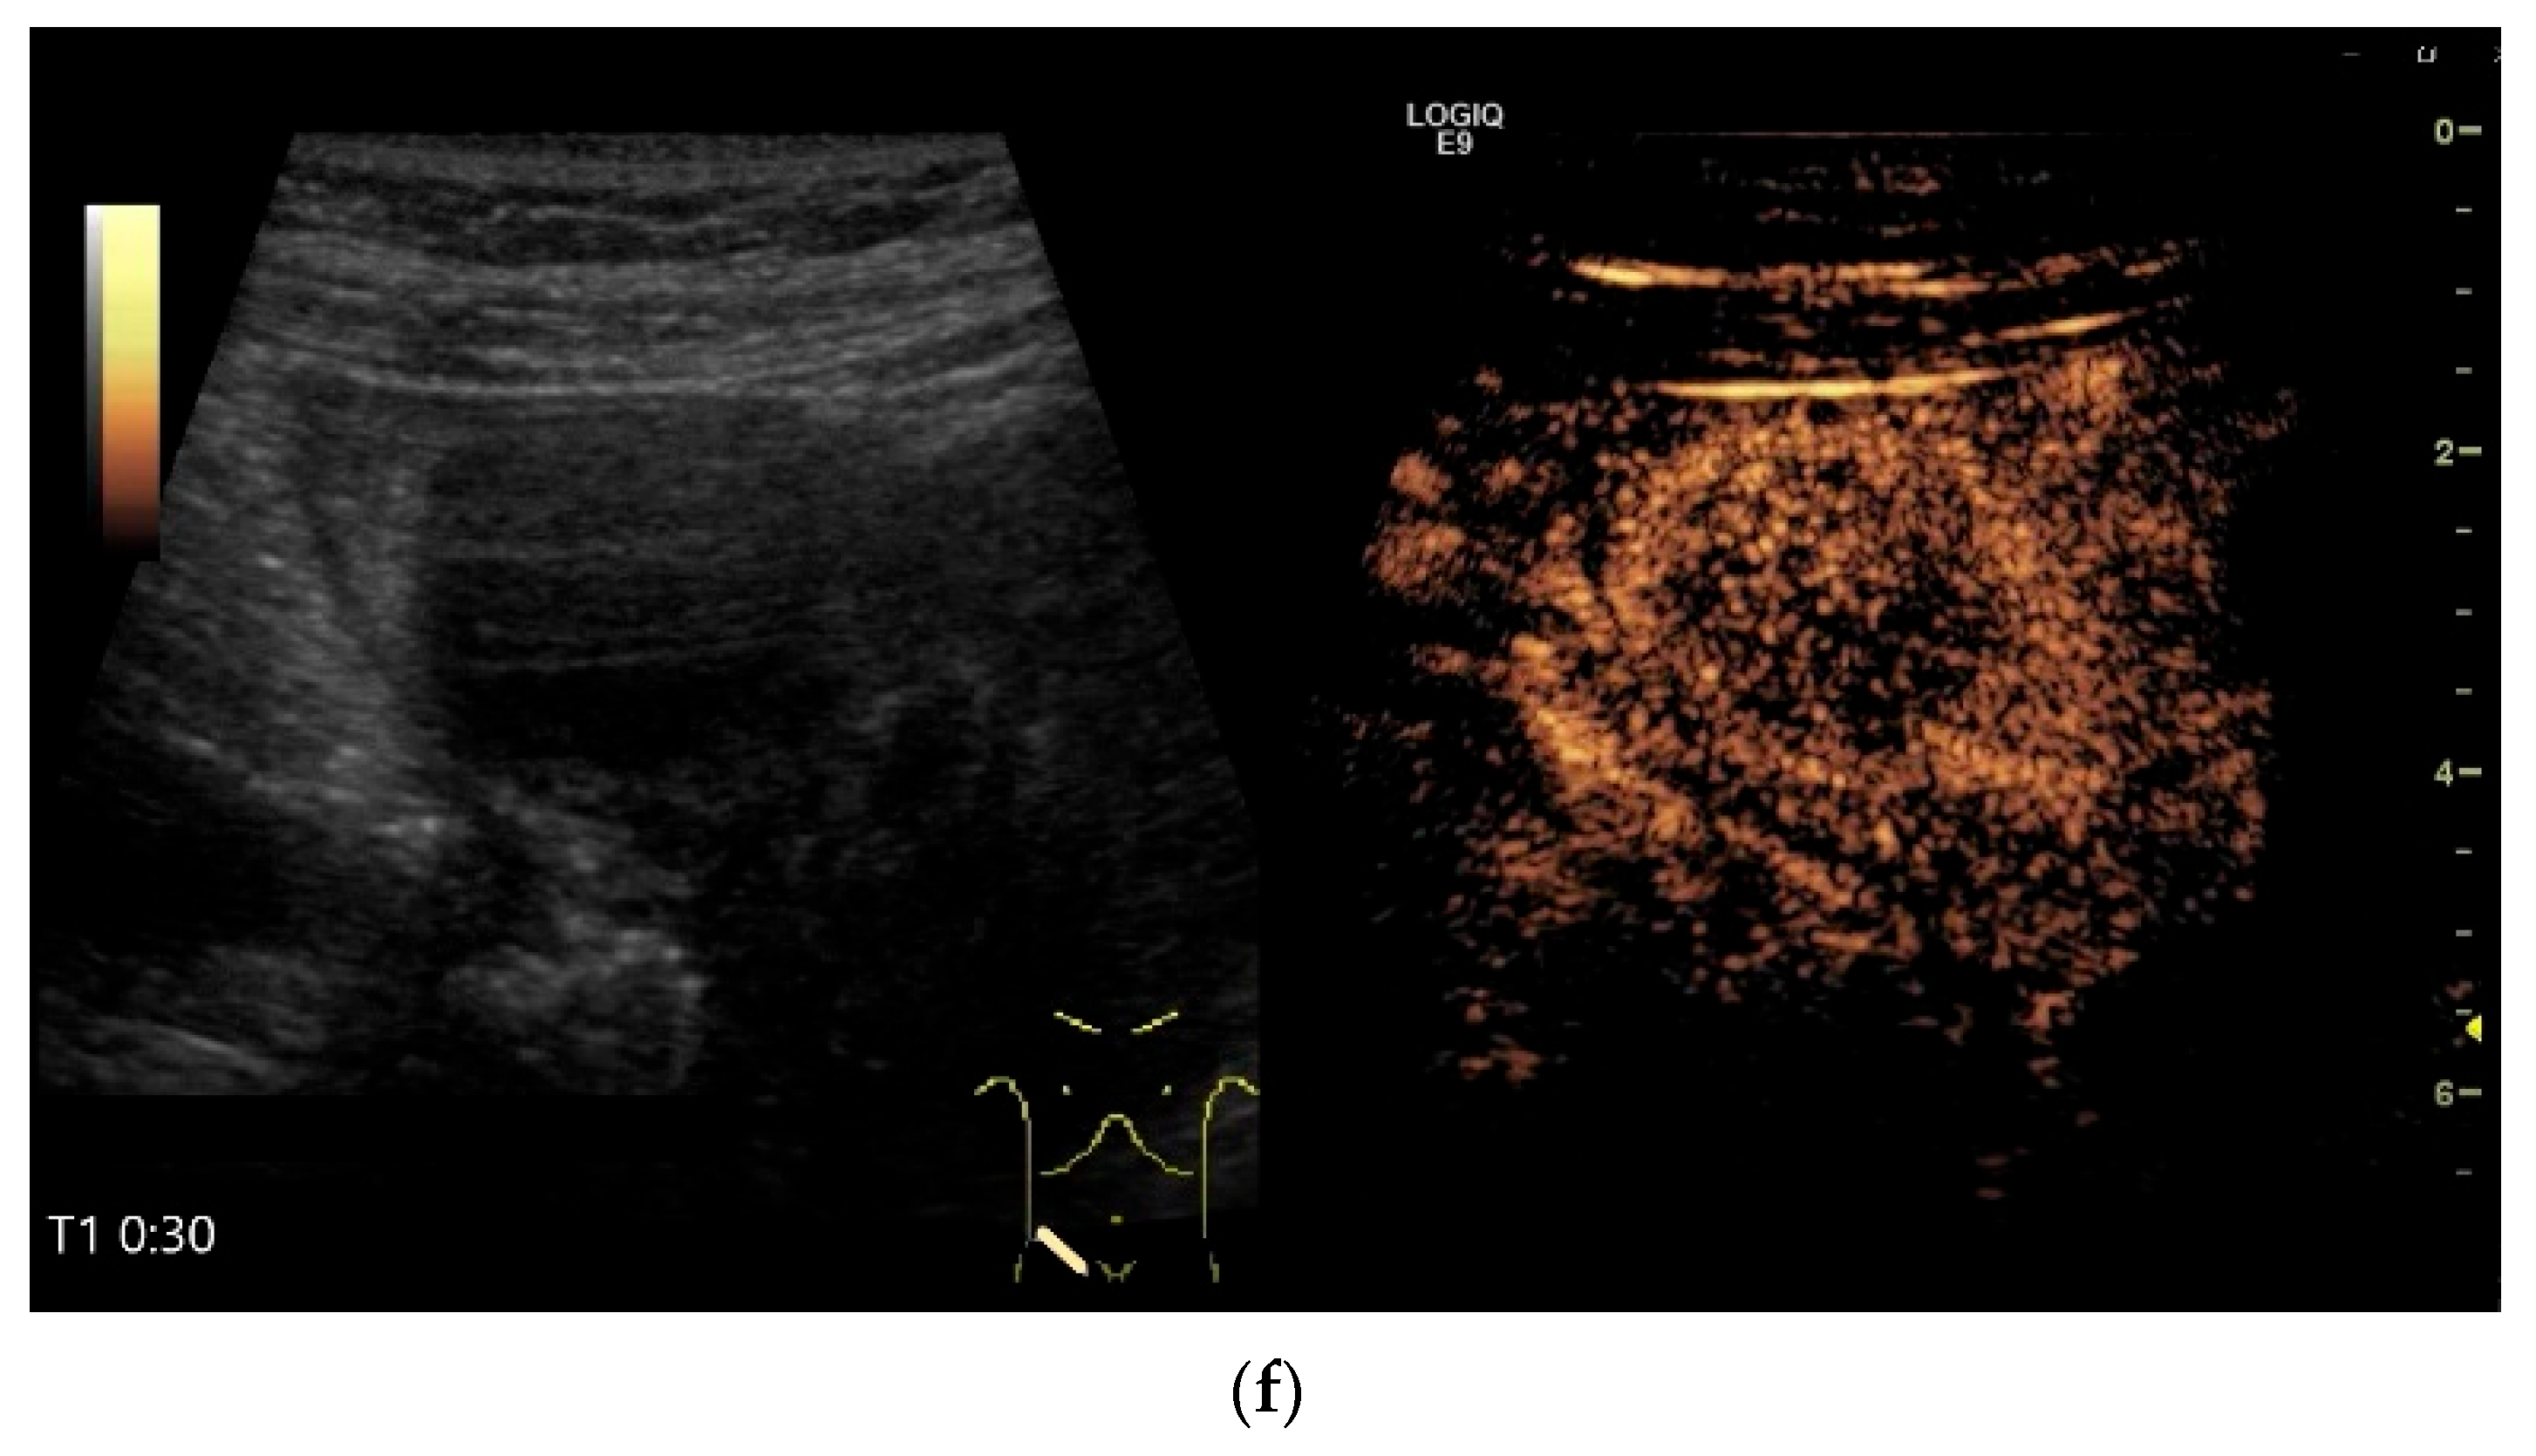

- Cui, N.Y.; Gong, X.T.; Tian, Y.T.; Wang, Y.; Zhang, R.; Liu, M.J.; Han, J.; Wang, B.; Yang, D. Contrast-enhanced ultrasound imaging for intestinal lymphoma. World J. Gastroenterol. 2021, 27, 5438–5447. [Google Scholar] [CrossRef]

| Lymphoma | Very pronounced wall thickening with marked hypoechogenicity. Large regional and distant lymph nodes. Look for splenic infiltration. Tumor vessels on CDI and hyperenhancement on CEUS. Heterogeneous hyperechogenicity of the mesentery with walling of the mesenteric vessels. Multiple localizations are possible. |